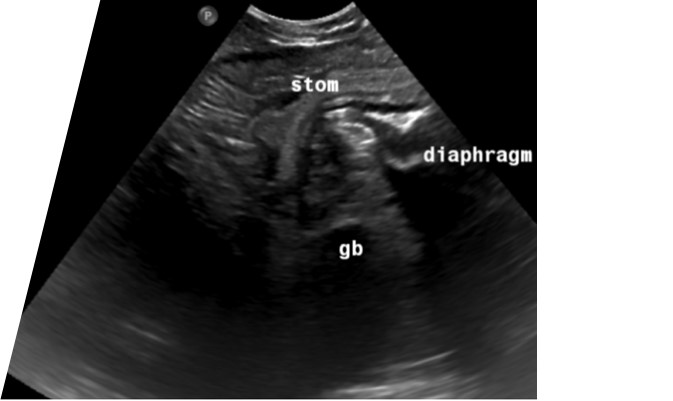

An abdominal ultrasound demonstrated a ventral mid-line diaphragmatic defect with herniation of the stomach, proximal duodenum, the spleen, the pancreas, and a portion of the liver including the left lobes and the gall bladder (figure 1).

Figure 1; Frozen image of ultrasound scan showing herniation of stomach and gall bladder through the diaphragmatic defect.